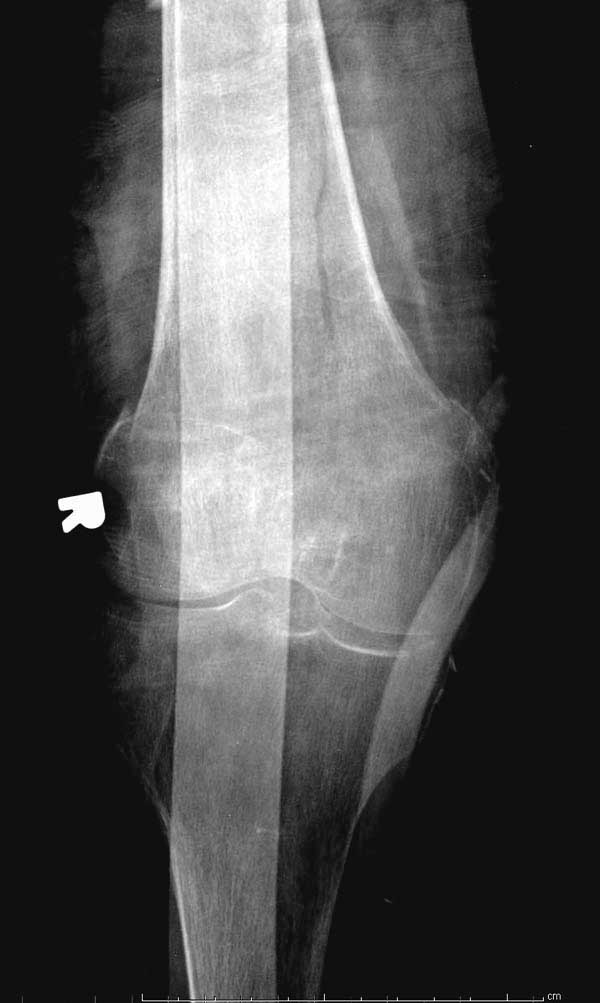

Обычно после чрезвертельных переломов, за исключением молодых, у пожилых остается нестабильность при движении. Часто падают и после 3х мес. в результате падения обнаружен перипротезный перелом (22-23), который зафиксирован Синтез пластиной.

Повторно поступает после двух с половиной лет, где обнаруживается перелом на второй стороне. Немного сложно, но для фиксации выбрали Antegrade InterTan Smith Nephew Nail и с момента фиксации более 3х мес.